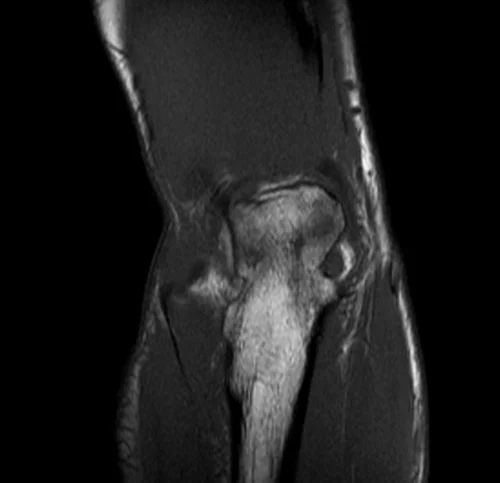

mri elbow coronal t1 image 1 - MRI